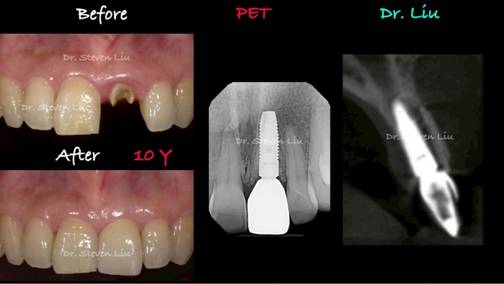

Dr. Liu’s clinical research activities focus on periodontal prosthesis concepts and implant dentistry, including aesthetic and anatomy concerns for implant surgery and prosthesis., also Zero bone loss in implant dentistry (3-20 years follow up).